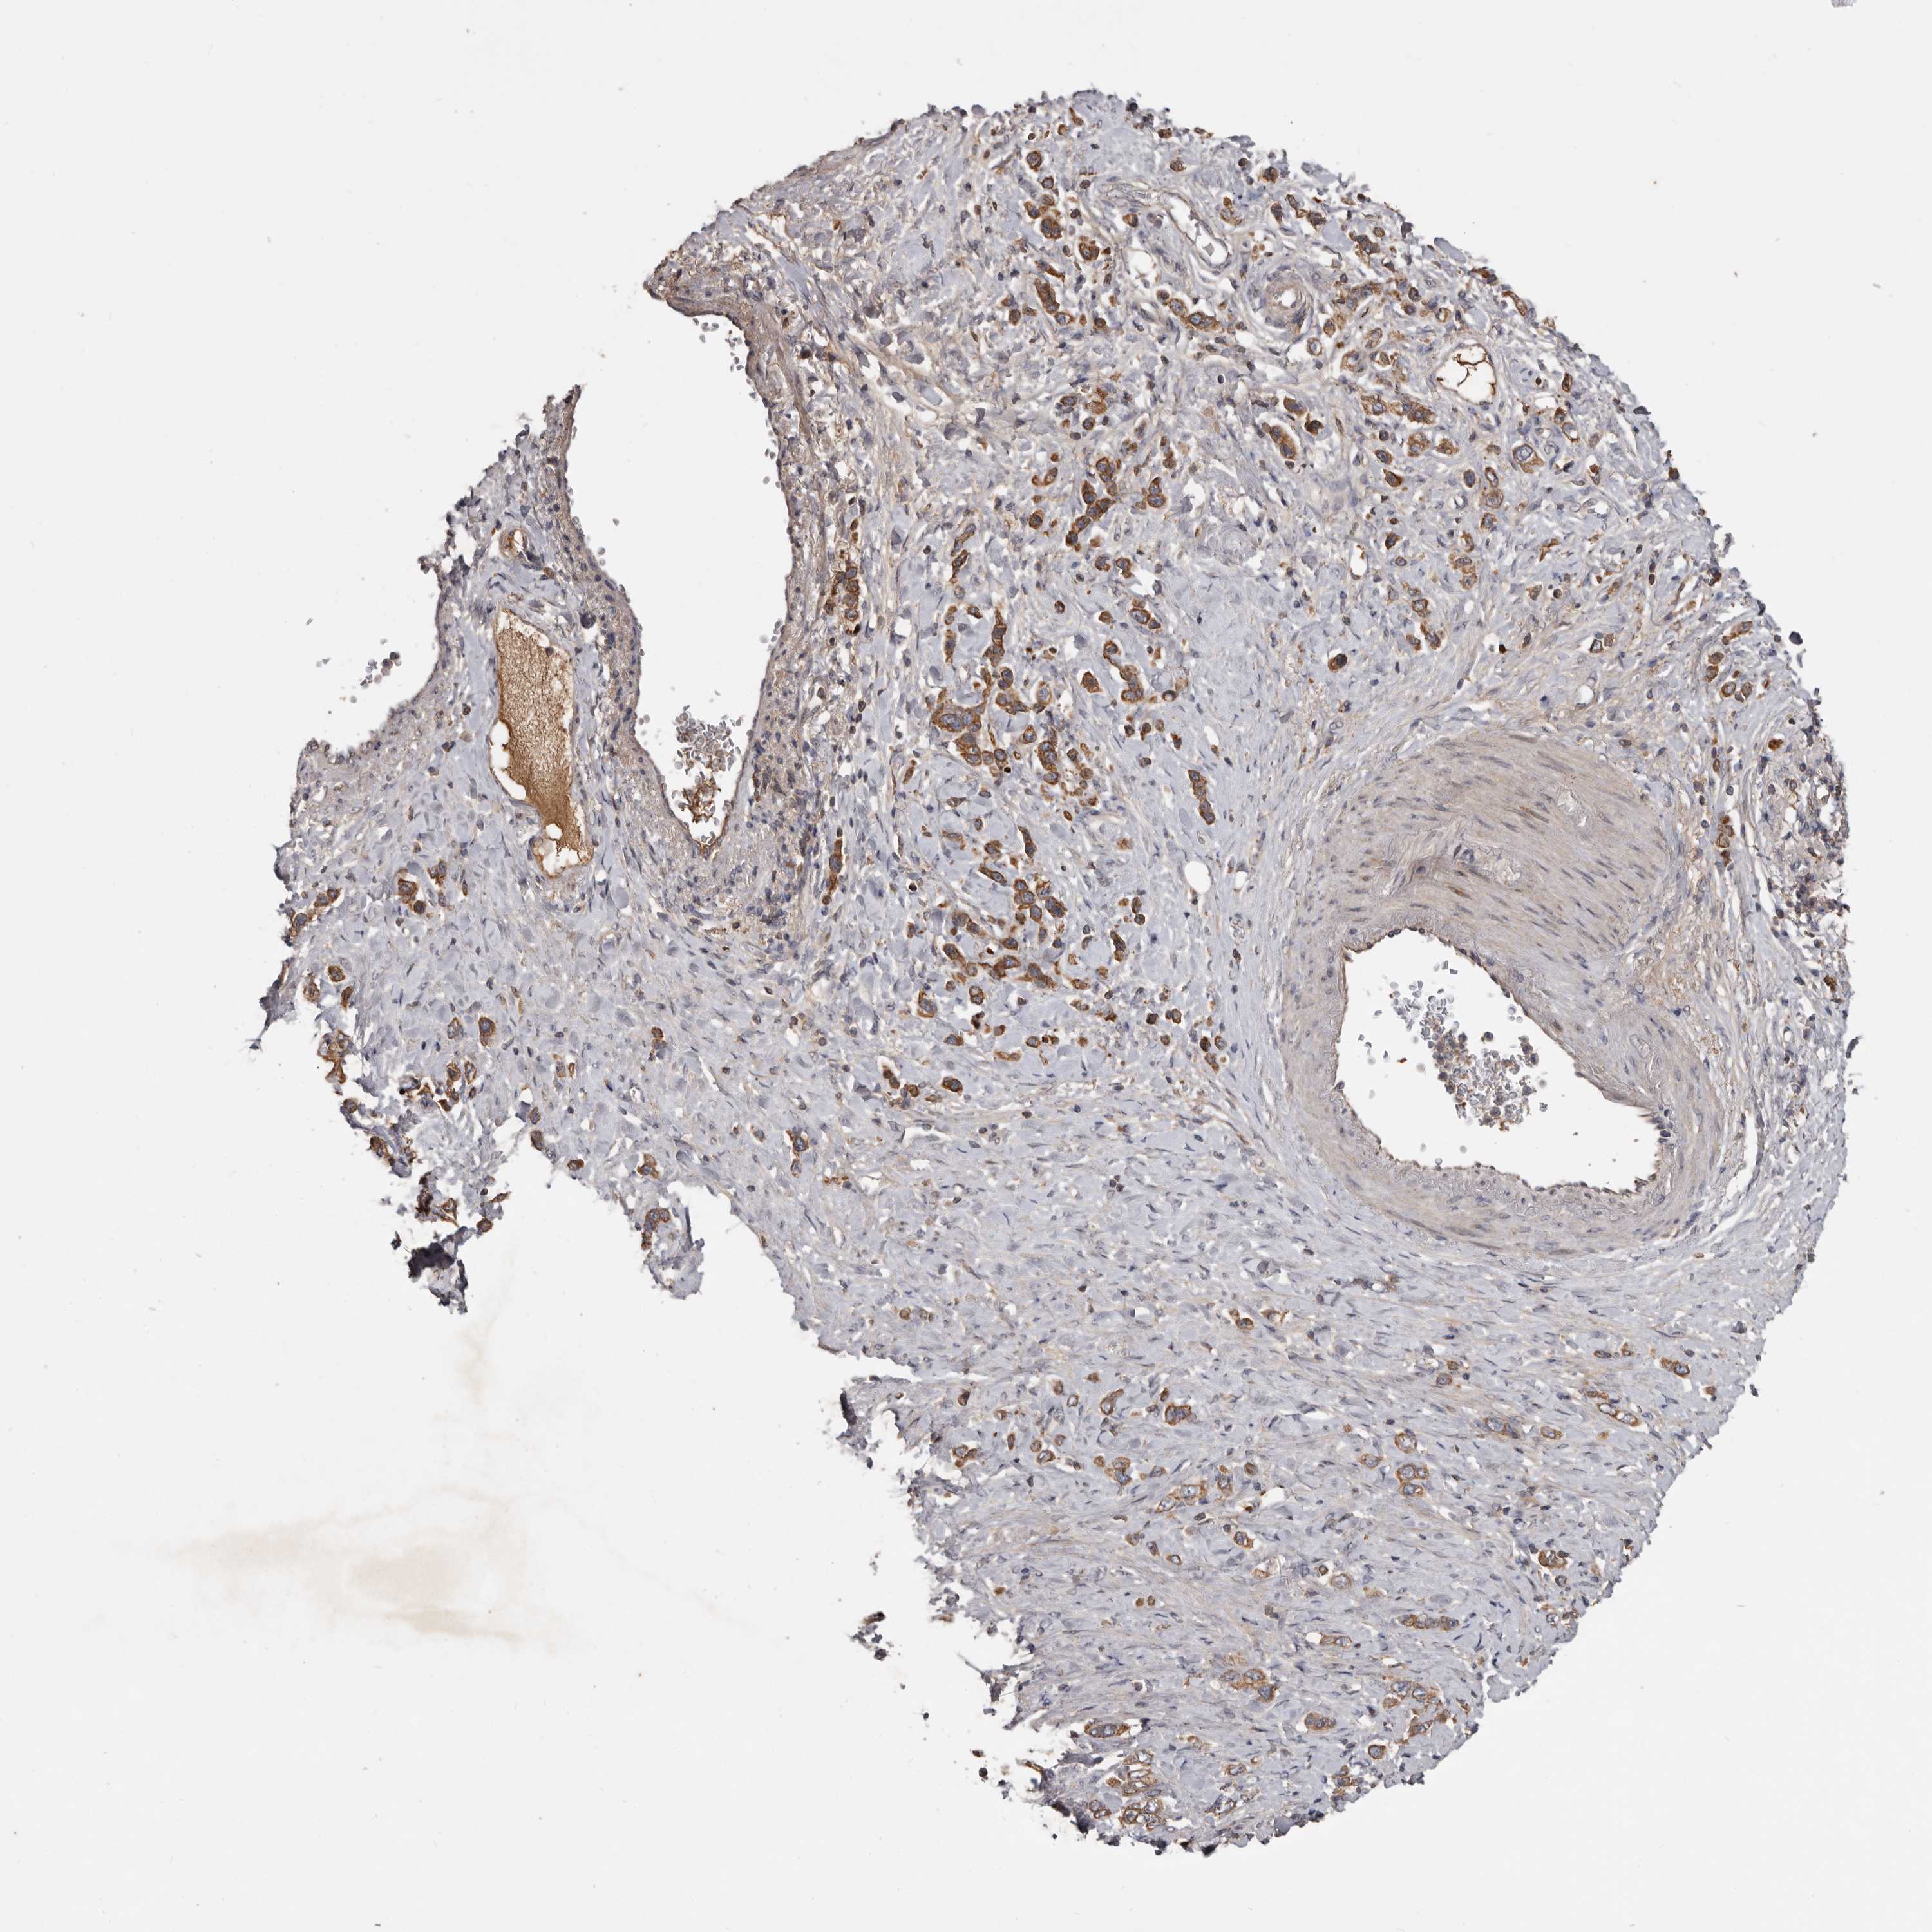

STOMACH CANCER - Protein expressioni

A mouse-over function shows sample information and annotation data. Click on an image to view it in a full screen mode. Samples can be filtered based on level of antibody staining by selecting one or several of the following categories: high, medium, low and not detected. The assay and annotation is described here.

Note that samples used for immunohistochemistry by the Human Protein Atlas do not correspond to samples in the TCGA dataset.

Antibody stainingi

Antibody staining in the annotated cell types in the current human tissue is reported as not detected, low, medium, or high, based on conventional immunohistochemistry profiling in selected tissues. This score is based on the combination of the staining intensity and fraction of stained cells.

Each image is clickable and will lead to virtual microscopy that enables deeper exploration of all samples and also displays staining intensity scores, fraction scores and subcellular localization as well as patient and tissue information for each sample.

Antibody HPA027895

Staining

High

Medium

Low

Not detected

Intensity

Strong

Moderate

Weak

Negative

Quantity

>75%

75%-25%

<25%

None

Location

Nuclear

Cytoplasmic/membranous

Cytoplasmic/membranous,nuclear

Adenocarcinoma, NOS